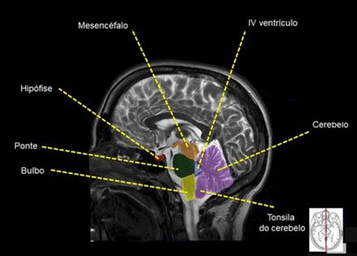

Imagem e estruturas Corte Sagital RM.